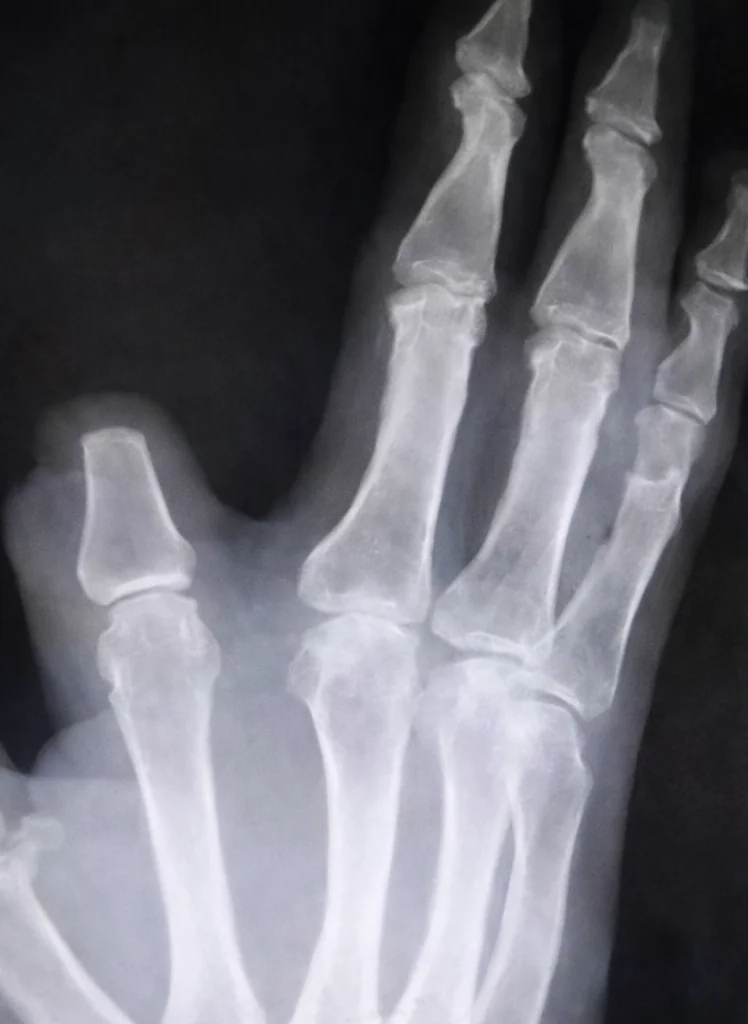

Um agricultor chinês de 60 anos, identificado apenas como Zhang, amputou parte do próprio dedo indicador após ser picado por uma cobra na zona rural de Shangyu, na província de Zhejiang. O incidente, ocorrido recentemente, foi motivado pelo temor de que o veneno da serpente se espalhasse pelo corpo. Após o ato, o homem percorreu cerca de 80 quilômetros até um hospital em Hangzhou em busca de socorro especializado.

O médico que prestou o atendimento, Yuan Chengda, lamentou a decisão precipitada do agricultor, ressaltando que o procedimento de amputação foi desnecessário. “Não era necessário cortar. Aquela cobra não é tão tóxica”, afirmou o profissional. Devido ao intervalo de tempo entre o incidente e a chegada à unidade de saúde, o pedaço do dedo removido não pôde ser reimplantado.